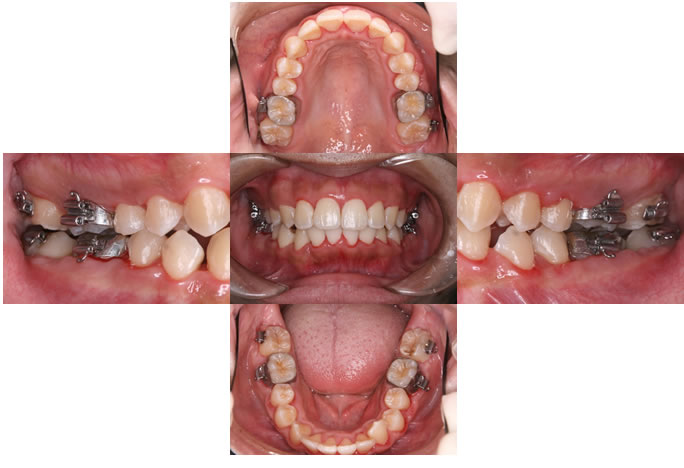

裁断すみです。汚れは目立ちませんが、何箇所か書き込みあり、裁断済みのため状態悪いとしています。- タイトル: 歯周矯正 GPがすべき五つの矯正治療- 著者: 前田早智子- 出版社: クインテッセンス出版- 言語: 日本語-定価19000円ご覧いただきありがとうございます。